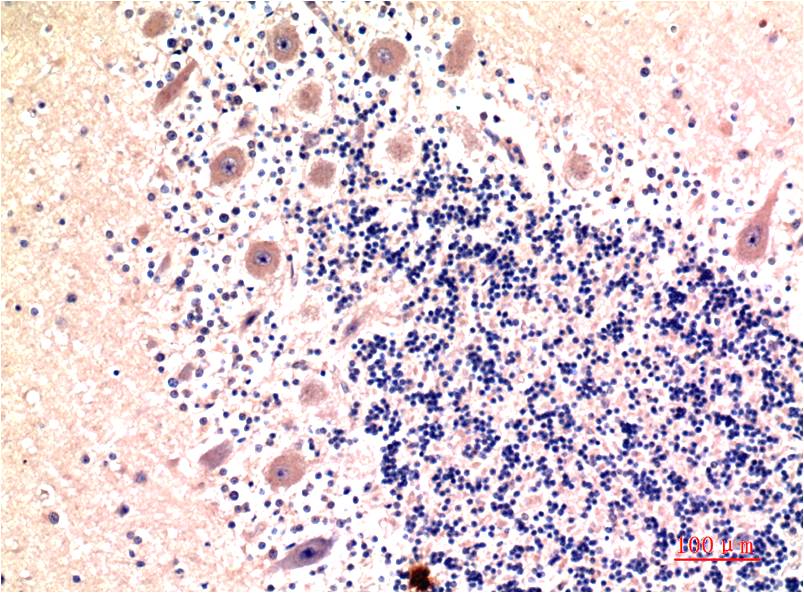

LC3B (9H5) Mouse mAb

Autophagy marker Light Chain 3 (LC3) was originally identified as a subunit of microtubule-associated proteins 1A and 1B (termed MAP1LC3).

IHC

IHC 1:100-200